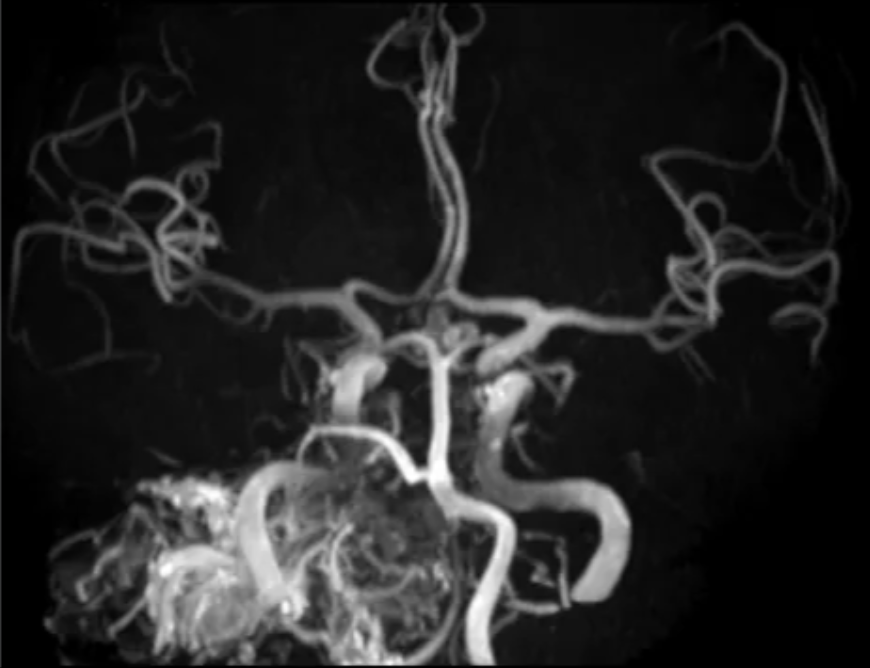

二是肿瘤血供异常丰富,10多根血管深入瘤体缠结,手术中将出血凶猛;

面对该患者严峻且复杂的病情,经过缜密研讨后,高亮教授团队确立了 “风险分层,精准控制” 的核心策略,制定了三步走的精准方案:

先介入栓塞降低肿瘤血供控制出血风险,再分块切除肿瘤,术中实时神经电生理监测提供动态防护。环环相扣的方案,以确保手术在可控的轨道上稳步推进。两场手术就此展开。

成功的栓塞

是开启肿瘤切除高难度手术的钥匙

第一场颅内血管栓塞术由神经介入团队操刀。盖延廷主任操作微导管精准超选多根肿瘤供血动脉,共注入26支医用栓塞胶阻断血流,这相当于一般性复杂手术用量的6倍!整个手术过程耗时8个小时,需要无比精细的手上感觉和极大的耐心。